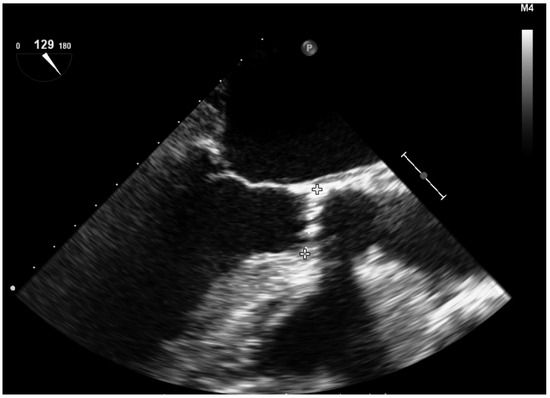

- Confirm the correct position of the prosthesis prior to inflation. However, it is not always easy to identify the ends of the prosthesis when it is still retracted on the balloon. The 3D mode will help in the correct identification of its ends (Video S10). If the prosthesis is too low, it can affect the mitral valve, and if it is too high, it can migrate distally or cause coronary obstruction. It should be taken into account that during inflation the prosthesis usually moves about 3 mm in the aortic direction.